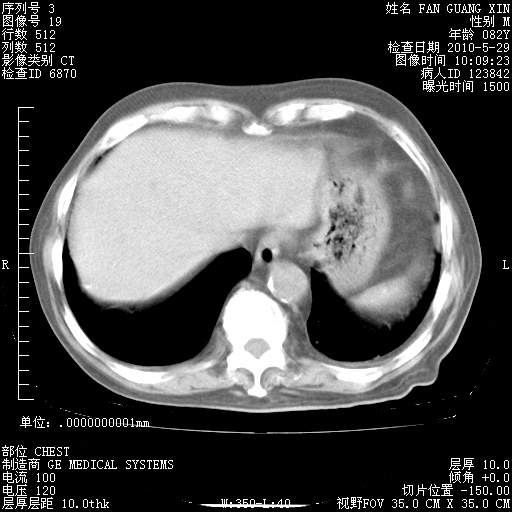

再治疗10天后的肺部CT

再治疗10天后的肺部CT 纵膈窗

从白细胞总数和中性比例看好像合并感染。肺部纹理好像比上次多,支气管炎?其他感染?

阅读此次胸部CT,肺间质渗出性改变较入院时有吸收。目前从体温、白细胞、中性分叶明显增高,肯定存在细菌感染(发生医院感染哦,若无消化道及泌尿系统等感染的依据,肺部感染可能大)。若你院头孢哌酮舒巴坦钠耐药率较高,同意你的方案,若48小时体温仍高,可考虑使用碳青霉稀类抗菌药物,同时可予超声雾化、注意滴数时加大液体量。白蛋白33.30g/L较低哦,需加强营养等支持治疗。